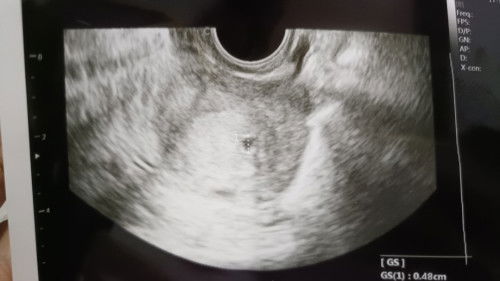

Menurut hpht 7 Minggu Pas di USG transv hasilnya 4 Minggu baru kantong kecil GS: 0.48 cm Normalkah? Kata dr nya disuruh balik blm depan Jdi was" Minta doa ya Bun🙏🤲